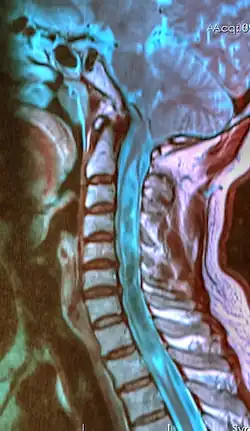

![]() | |

| A sagittal FLAIR MRI scan, from a patient with an Arnold–Chiari malformation, demonstrating tonsillar herniation of 7 mm. | |

Diagnosis is made through a combination of patient history, neurological examination, and medical imaging.[27][28] Magnetic resonance imaging (MRI) is considered the preferred imaging modality for Chiari malformation.[29] The MRI visualizes neural tissue such as the cerebellar tonsils and spinal cord as well as bone and other soft tissues. CT and CT myelography are other options and were used prior to the advent of MRI, unfortunately the resolution of CT based modalities do not characterize syringomyelia and other neural abnormalities as well.[30]

By convention, the cerebellar tonsil position is measured relative to the basion-opisthion line, using sagittal T1 MRI images or sagittal CT images.[31] The selected cutoff distance for abnormal tonsil position is somewhat arbitrary, as not every person will be symptomatic at a certain amount of tonsil displacement, and the probability of symptoms and syrinx increases with greater displacement; however, greater than 5 mm is the most frequently cited cutoff number, though some consider 3–5 mm to be "borderline"; pathological signs and syrinx may occur beyond that distance.[31][32][33] One study showed little difference in cerebellar tonsil position between standard recumbent MRI and upright MRI for patients without a history of whiplash injury.[25] Neuroradiological investigation is used to rule out any intracranial condition that could be responsible for tonsillar herniation first. Neuroradiological diagnostics evaluate the severity of crowding of the neural structures within the posterior cranial fossa and their pressure against the foramen magnum. Chiari 1.5 is a term used when both brainstem and tonsillar herniation through the foramen magnum are present.[34]